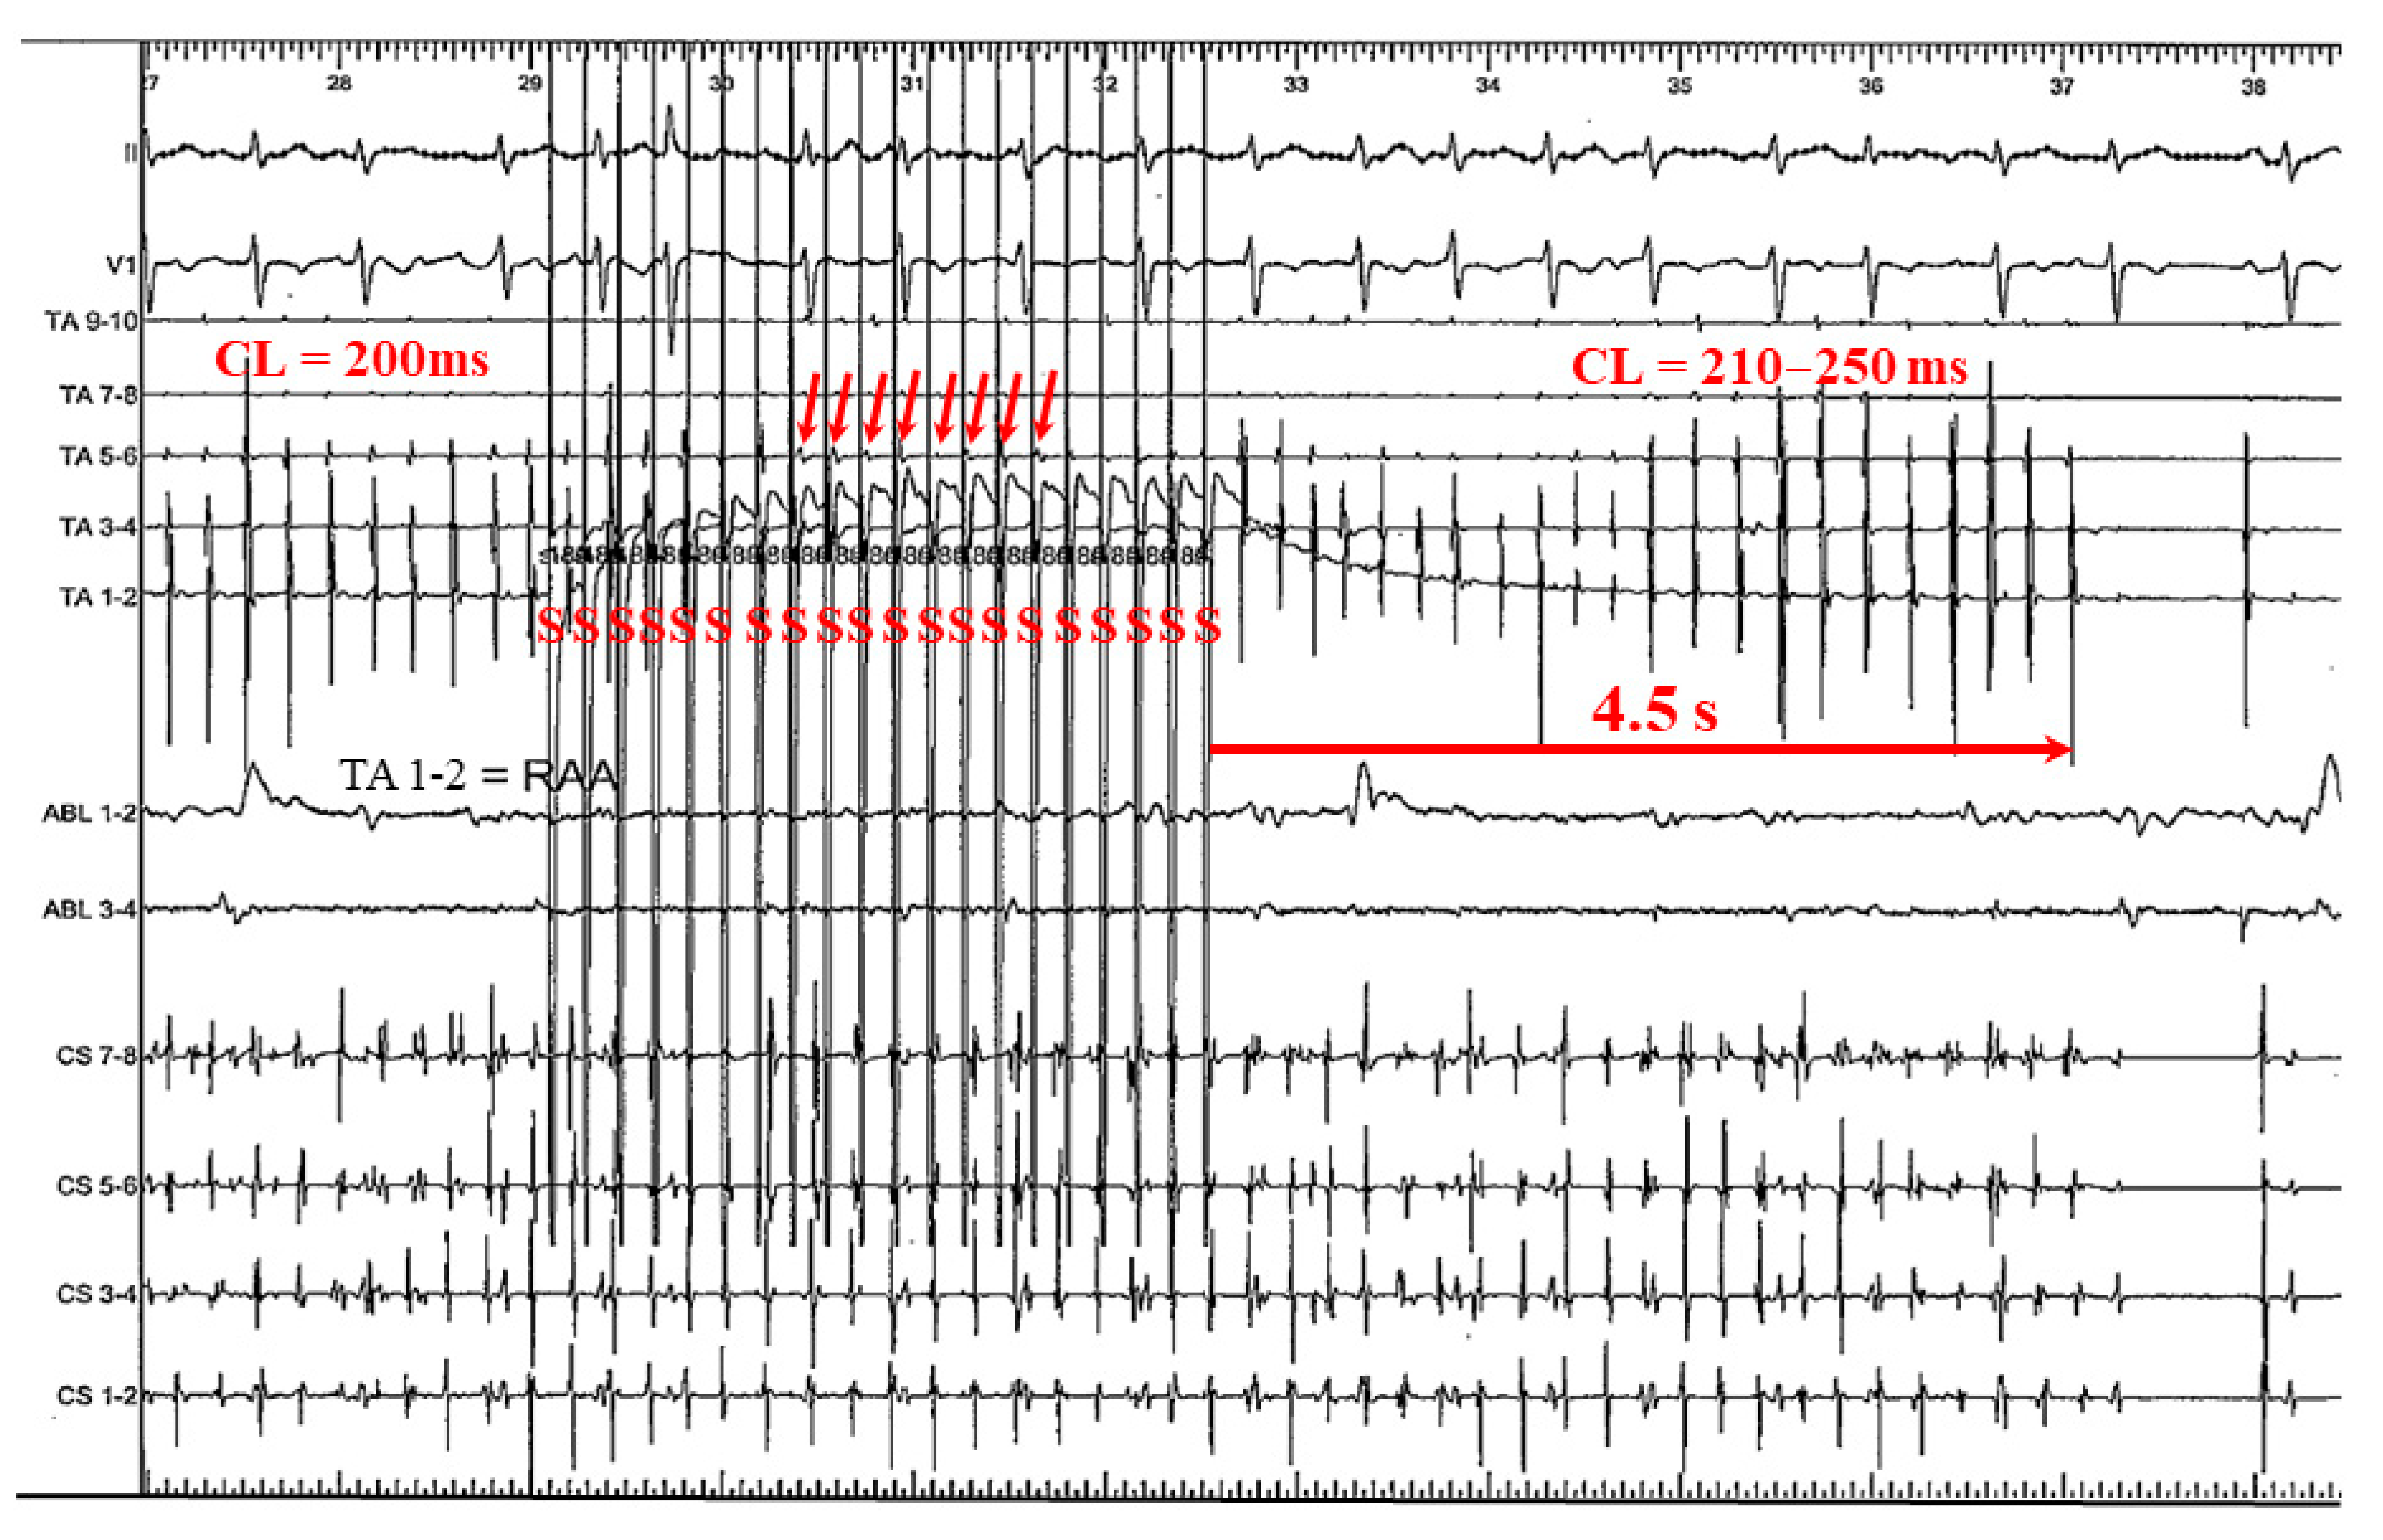

3.2.3. Case 3: 67-Year-Old Man with Symptomatic PAF